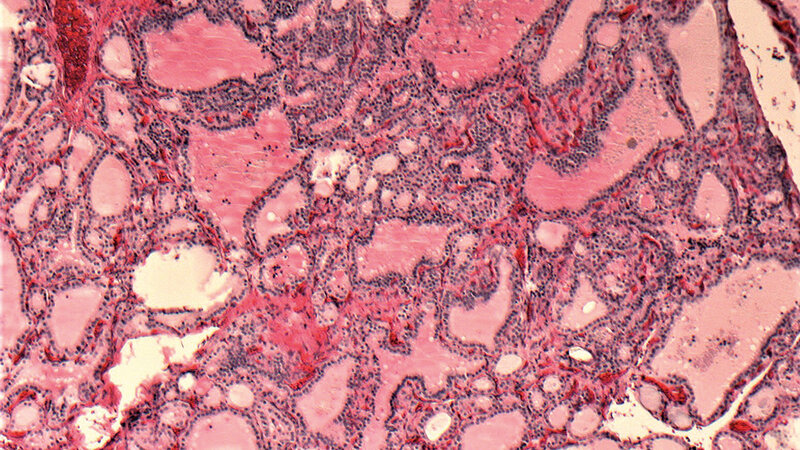

Neben den bereits erwähnten Schilddrüsenerkrankungen können in der Schilddrüse auch benigne und maligne Tumoren entstehen. Das papilläre Schilddrüsenkarzinom ist, außerhalb der Struma-Endemiegebiete, mit 70–80 % der häufigste maligne Tumor in der Schilddrüse. Zur Unterscheidung, um welche Art von Tumor es sich handelt und ob es wirklich ein primärer Schilddrüsentumor ist, ist das histologische Bild dieses Tumors das erste ausschlaggebende Kriterium. Der Einsatz der Immunhistochemie zur Differenzialdiagnose ist aus der Routinediagnostik nicht mehr wegzudenken. Die Molekularpathologie spielt ebenfalls immer häufiger eine wichtige Rolle bei der Diagnose und der Therapie.

In addition to the previously mentioned thyroid disorders, benign and malignant tumors can also develop in the thyroid gland. Outside the struma endemic fields the most common malign tumor is the papillary thyroid carcinoma. To distinguish which type of tumor is involved and whether it is really a primary thyroid tumor, the histological picture of this tumor is the first decisive criterion. In addition, the use of immunohistochemistry for differential diagnosis is indispensable in routine diagnostics today. The molecular pathology is becoming more and more important in diagnosis and therapy.